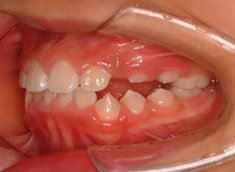

治療後(1年3ヶ月後)

治療開始から約10ヶ月後